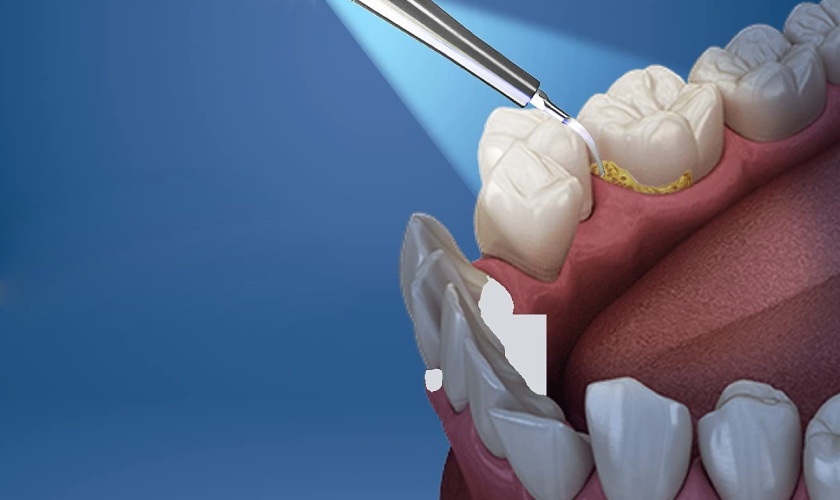

Cạo vôi răng là quy trình nha khoa nhằm loại bỏ mảng bám và vôi răng tích tụ trên bề mặt răng. Mảng bám là một lớp chất dơ mềm chứa vi khuẩn, nếu không được làm sạch thường xuyên, chúng có thể cứng lại và hình thành vôi răng. Vôi răng không chỉ gây mất thẩm mỹ mà còn tạo điều kiện cho các bệnh lý răng miệng như sâu răng, viêm nướu, và viêm nha chu phát triển.

Quy trình cạo vôi răng thường được thực hiện bởi các nha sĩ hoặc nhân viên nha khoa. Sau khi kiểm tra tình trạng răng miệng, nha sĩ sẽ sử dụng các dụng cụ chuyên dụng để loại bỏ vôi răng một cách an toàn và hiệu quả. Thời gian thực hiện thường chỉ kéo dài từ 30 phút đến 1 giờ, tùy thuộc vào mức độ tích tụ vôi.

Hình ảnh giới thiệu về cạo vôi răng